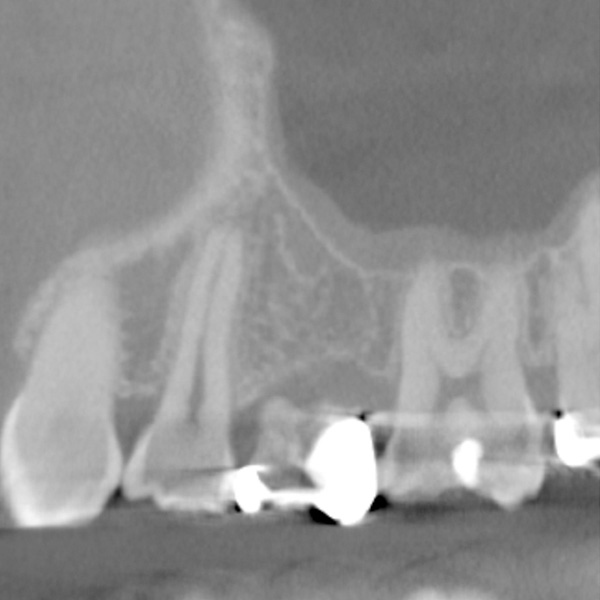

| 年代・性別 | 50代 男性 |

|---|---|

| 主訴 | 前医で前歯を抜かなければならないがインプラントはできないと言われた |

| 治療期間 | 約12ヶ月 |

| 費用 | 600,000円 |

| 治療内容 | インプラント、骨造成、結合組織移植、セラミック修復 |

| 治療に伴うリスク | インプラント周囲炎 セラミックの破折、脱離 |